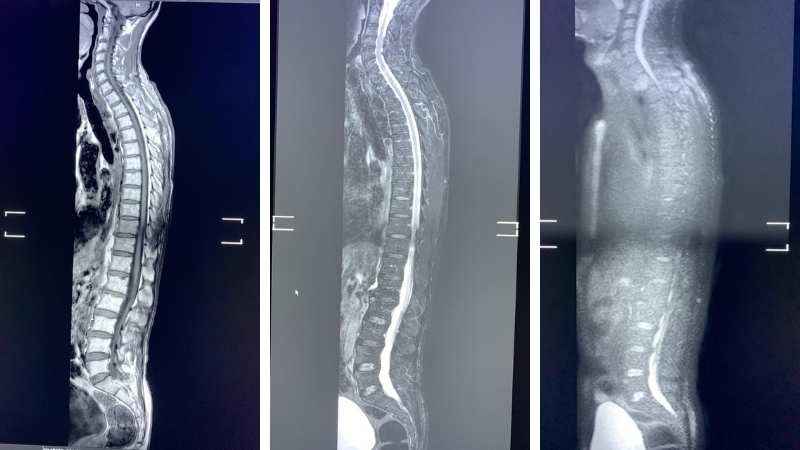

Hospital Parque Vegas Altas de Don Benito amplía la Cartera de Servicios de su Resonancia Magnética de última generación Ingenia Philips de su Servicio de Radiología:

- Introducce la RM de Cuerpo Entero-Difusión, una técnica muy prometedora en la detección y monitorización terapéutica de las metástasis óseas del cáncer de próstata y de mama y que no precisa de radiaciones ionizantes ni de la administración de contraste intravenoso.

La principal indicación de la RM de cuerpo entero-difusión es valorar todo el cuerpo desde la cabeza a los pies y poder estudiar tanto el esqueleto óseo como las partes blandas, músculos y órganos en un solo estudio.

Ha demostrado su papel frente al PET-TAC y un papel especialmente relevante en el estudio de las metástasis óseas y el mieloma múltiple por su excelente resolución de contraste y la gran capacidad en detección de lesiones óseas incluso sin gran actividad metabólica. Incorpora la difusión de cuerpo entero como un potente bio marcador oncológico y monitorización terapéutica y en cribados oncológicos.

Incorpora la Difusión de cuerpo entero como un potente biomarcador oncológico y de monitorización terapéutica y en cribados con el cálculo del ADC, así como aportar la información funcional que mejora la sensibilidad en la detección de lesiones oncológicas y de las metástasis osteolíticas y permite evaluar la respuesta al tratamiento.